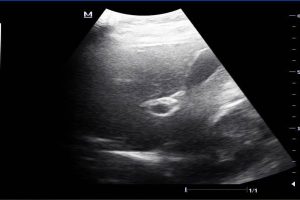

Diplomados en Ultrasonografía